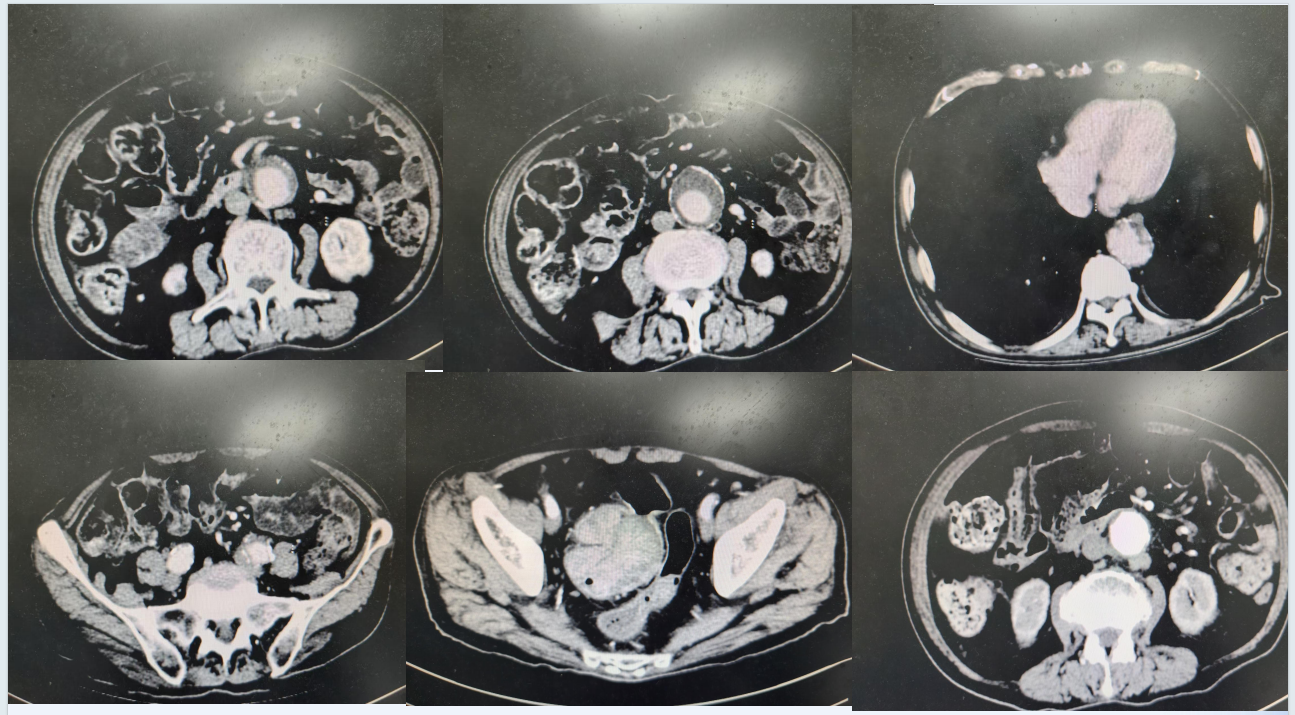

结肠镜检(2024年3月):距肛门24-36cm见巨大粘膜肿物,形态欠规则,肠腔狭窄,行活检;距肛门15cm左右见头端2.5cm粗蒂粘膜隆起,头端局部糜烂,活检;镜下诊断:乙状结肠占位。病理提示:乙状结肠腺癌,直肠巨大息肉。胸腹部CT(2024年3月16日):双肺气肿、肺大泡,双肺多发小结节;心包及双侧胸腔少量积液;腹主动脉及髂总动脉局部瘤样扩张,提示动脉瘤形成并附壁血栓可能性大,双侧髂内动脉局部未见明确显影,提示闭塞,腹膜后淋巴结增大。乙状结肠腔内团状密度增高影,局部扩张,占位合并出血不除外(图4)。

图4. 胸腹部CT检查(2024年3月16日)